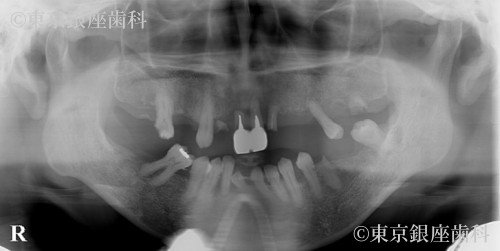

数年以上にわたり、歯科医院に通院できなかったため、全顎的に歯周病が重度に進行してしまった。その結果、何本もの歯が自然に抜け落ちてしまい、また差し歯も外れてしまった。奥歯で安定して咬むことができず、咬み合わせることができる場所が前歯しかなかったので、長期にわたり前歯を中心に咀嚼を続けていた。その結果、前歯に対する過剰な負担がかかってしまい、前歯を支える周りの骨の著しい吸収と、前歯の位置の変化が認められた。また奥歯の支えがなく、顔の周囲の筋肉が十分な機能を果たしていなかったため、表情筋の張りが不足していることが認められた。

患者様の主訴である見た目の改善をするために、奥歯での咬み合わせを安定させることで、口腔機能の回復させ、同時に審美の改善もはかる計画を立てました。上下顎ともに残っている歯のほとんどが重度の歯周病と過剰な咬み合わせの力により、歯の周りの骨の吸収が著しかったため、全顎的な抜歯と、ワンデイインプラント治療による口腔機能・審美の改善をはかることを計画いたしました。また歯科治療に対する極度の恐怖症だったため、静脈内鎮静を併用することを予定しました。